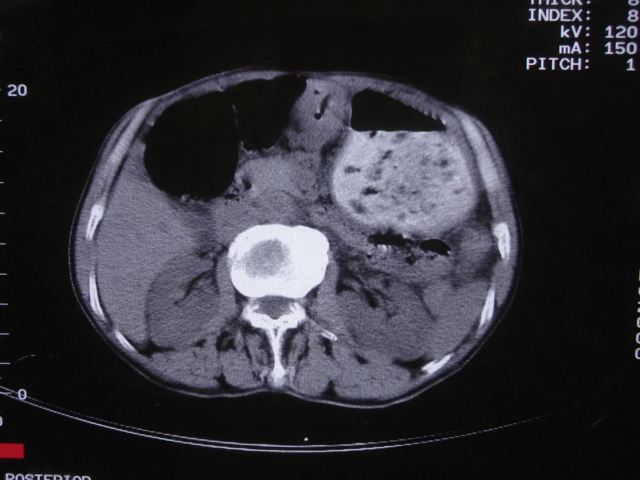

以下是引用深泽交通医院在2008-7-17 12:39:00的发言:[br]胃下垂;胃窦占位